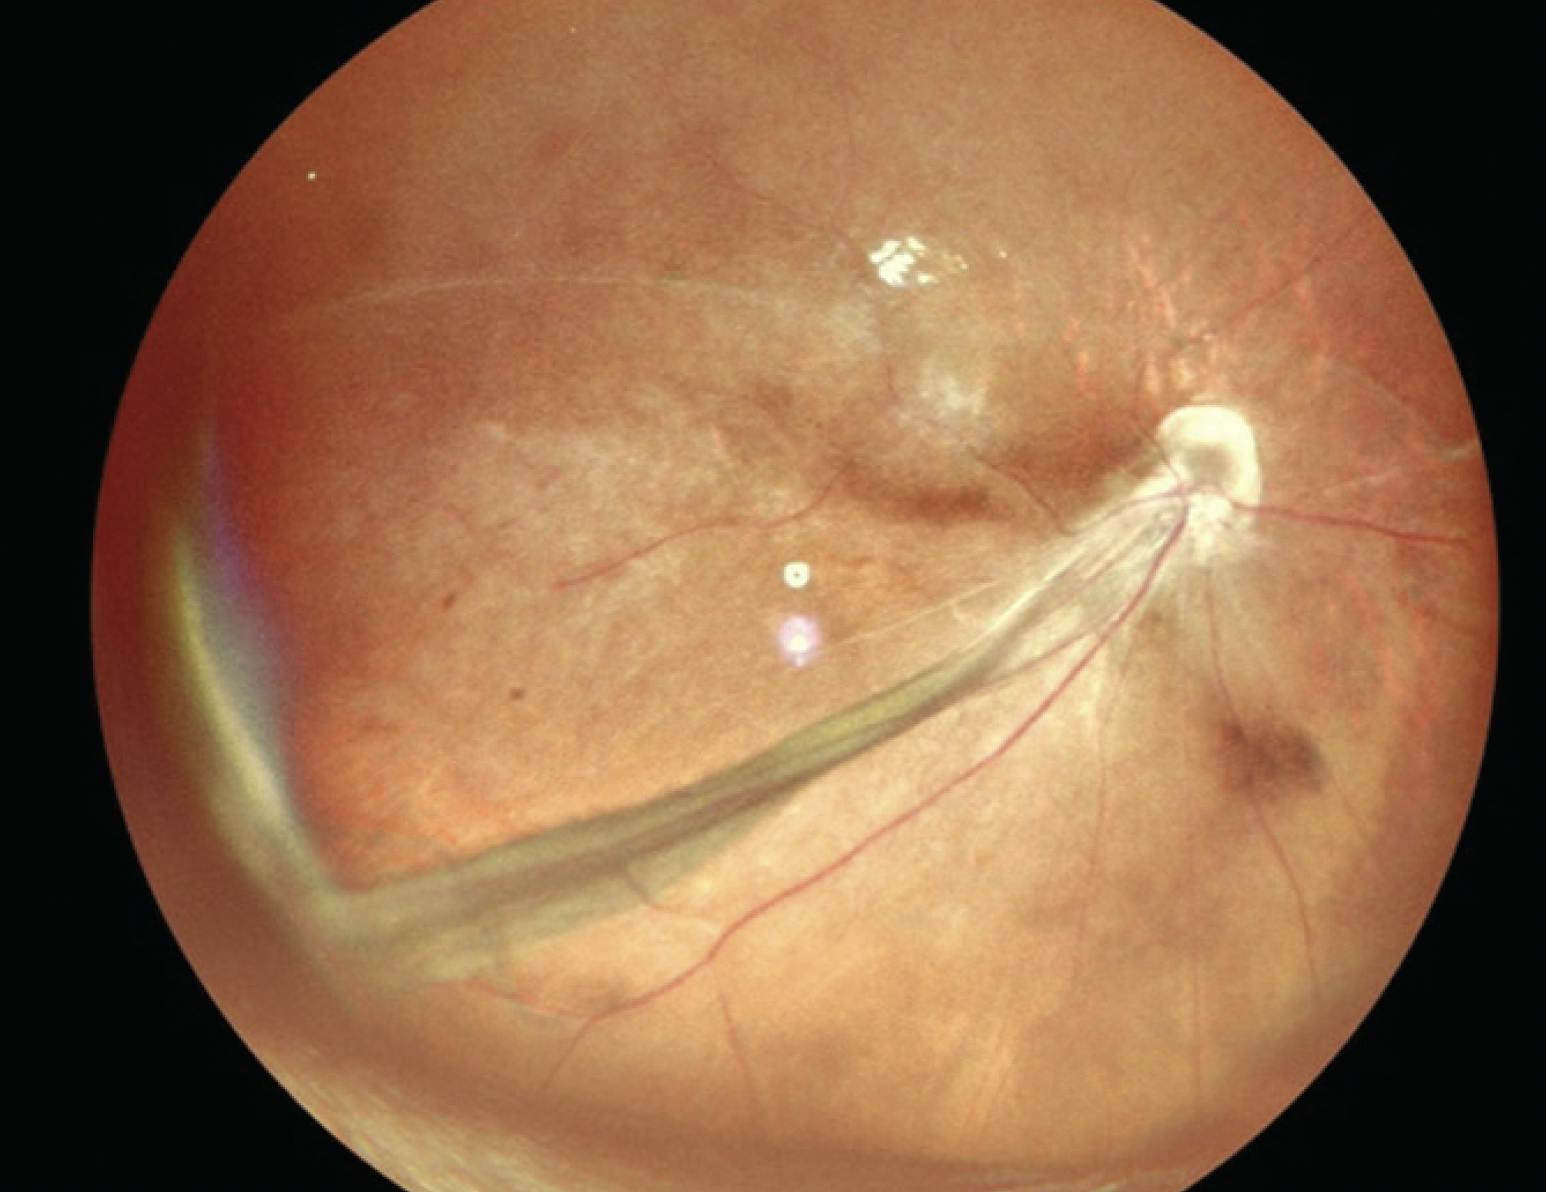

A 2.5-year-old boy presented with squinting in the left eye since birth. Dilated fundus examination revealed a fibrovascular stalk in the left eye extending from the disc to the posterior capsule of the lens suggestive of persistent hyperplastic primary vitreous (Figure 2). OCT showed an altered foveal contour. Ultrasound of the left eye showed membranous echoes with low to moderate spikes and restricted movements suggestive of persistent hyperplastic primary vitreous. The patient was advised to undergo refraction, use low vision aids, and follow up every 6 months.

<p>Figure 2. Widefield imaging of the left eye shows a fibrovascular stalk extending from the optic disc to the posterior capsule of the lens.</p>

Figure 2. Widefield imaging of the left eye shows a fibrovascular stalk extending from the optic disc to the posterior capsule of the lens.